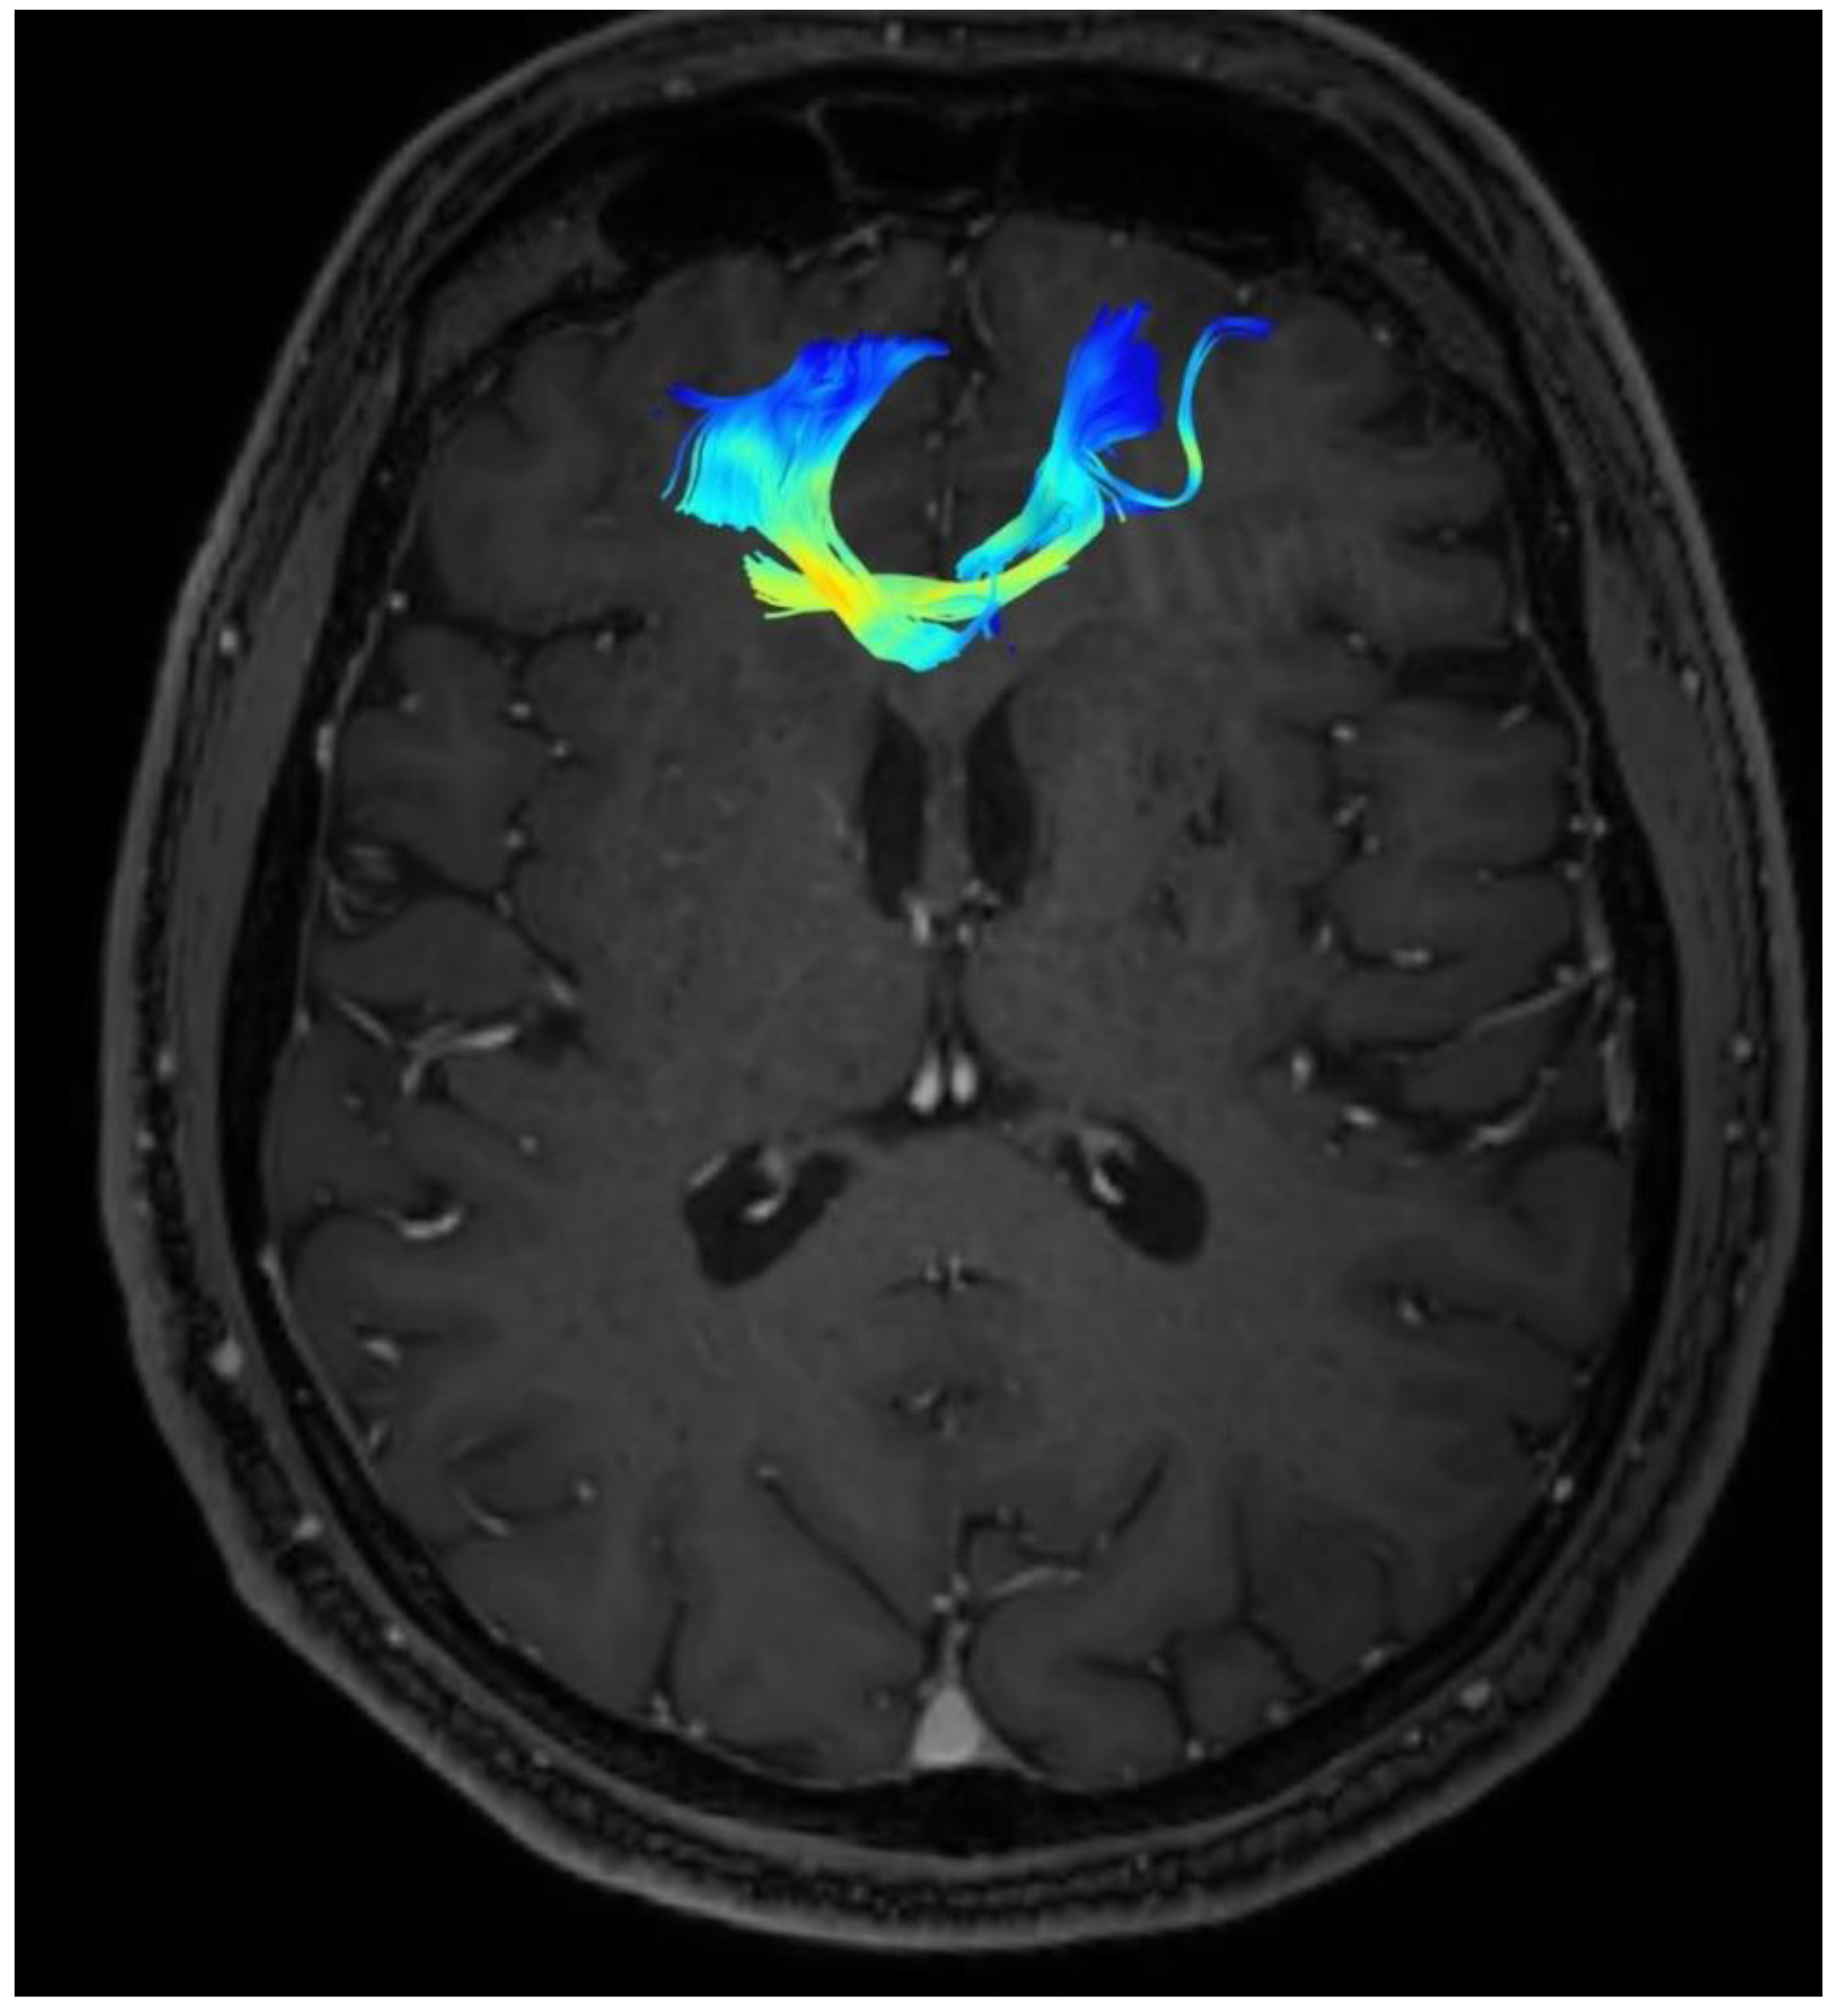

Changes in the anatomy of forceps minor before and after cingulotomy are presented in Figure 2 and Figure 3; moreover, arcuate fasciculus before and after cingulotomy is presented in Figure 4 and Figure 5.

Figure 5. Arcuate fasciculus after cingulotomy.

Brainsci 13 00044 g005